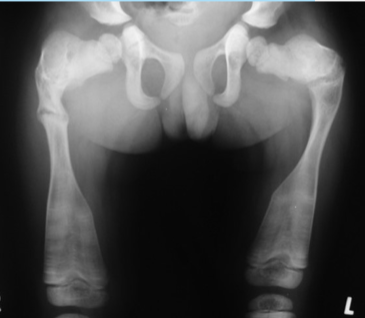

Rad - DDH

AP views

evaluated with Perkin’s, Hilgenreiner’s, Shenton’s line